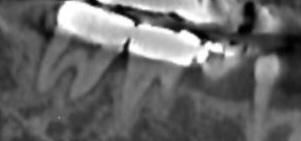

이 이빨의 상태를 알고싶습니다.부탁드려요

잇몸치료받고잇습니다 치아상태가 많이안좋은가요?

염증이 잇어보이는지 궁금합니다. 피곤하면 가끔 붓습니다.치간치실때 피가 가끔납니다.

안녕하세요. 김지훈 치과의사입니다.염증은 있는 것으로 보입니다. 증상이 지속적으로 나타나는 경우 치과에서 치료받으셔야 합니다.

치아의 주변 인대가 많이 확장된것으로 보이고 염증이 잇는거 같으니 일단 잇몸치료를 받아보시는게 좋을것같습니다.

사진으로 봤을 경우에는 심한 치주 질환이 보이진 않습니다. 하지만 불편감이 있다면 염증이 있을 가능성이 높기 때문 때문에 치과에서 치료를 받는 것이 좋습니다.

위 엑스레이보다는 치근단 엑스레이 사진이 있다면 좋습니다

증상으로는 잇몸에 염증이 있는 상태가 맞습니다